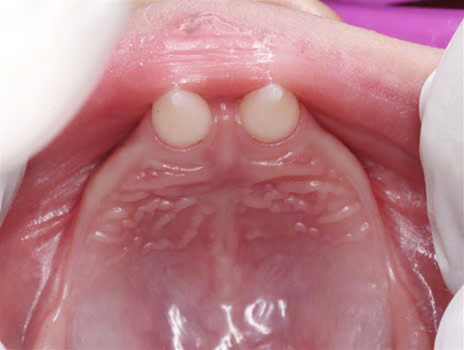

Hình 2: Ảnh chụp trong miệng

Trường hợp thiếu răng: răng trong miệng thường bị dị dạng, có dạng hình nón hoặc hình chóp.

Tùy mức độ từ nhẹ đến nặng của bệnh mà có biểu hiện ở răng từ thiếu một vài răng đến thiếu nhiều răng đến không có răng.